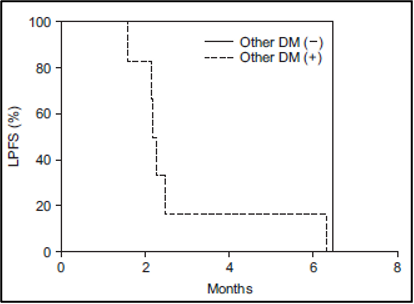

לאחר 3 חודשים, ההישרדות ללא התקדמות מקומית (LPFS) הייתה 30% וההישרדות ללא התקדמות כאב (PPFS) הייתה 58.3%. גורמים פרוגנוסטיים אפשריים הקשורים לשיעורי ההישרדות נמצאים בטבלה 3. עלייה בדירוג צ'יילד-פו (Child-Pugh score) (p = 0.04) (איור 5A) בחודש אחד לאחר טיפול קרינתי לכל הכבד (WLI) עם היפרתרמיה היה גורם פרוגנוסטי משמעותי להישרדות ללא התקדמות מקומית (LPFS). הישרדות ללא התקדמות מקומית (LPFS) נוטה להיות גבוהה יותר במטופלים ללא גרורות חוץ-כבדיות משולבות (combined extrahepatic metastasis) (p = 0.1) (איור משלים 1).

להלן איור 5: עקומות ההישרדות של קפלן-מאיר בהתאם לגורמים פרוגנוסטיים מובהקים. (A) עלייה בדירוג צ'יילד-פו (CP) בחודש אחד על ההישרדות ללא התקדמות מקומית (LPFS), (B) נפח כבד שלם (Whole liver volume) גדול מ-3,000 מ"ל המייצג נפח גידול גרורתי על ההישרדות ללא התקדמות כאב (PPFS)

איור משלים 1: עקומת ההישרדות של קפלן-מאיר של ההישרדות ללא התקדמות מקומית (LPFS) בהתאם לנוכחות של גרורות חוץ כבדיות משולבות